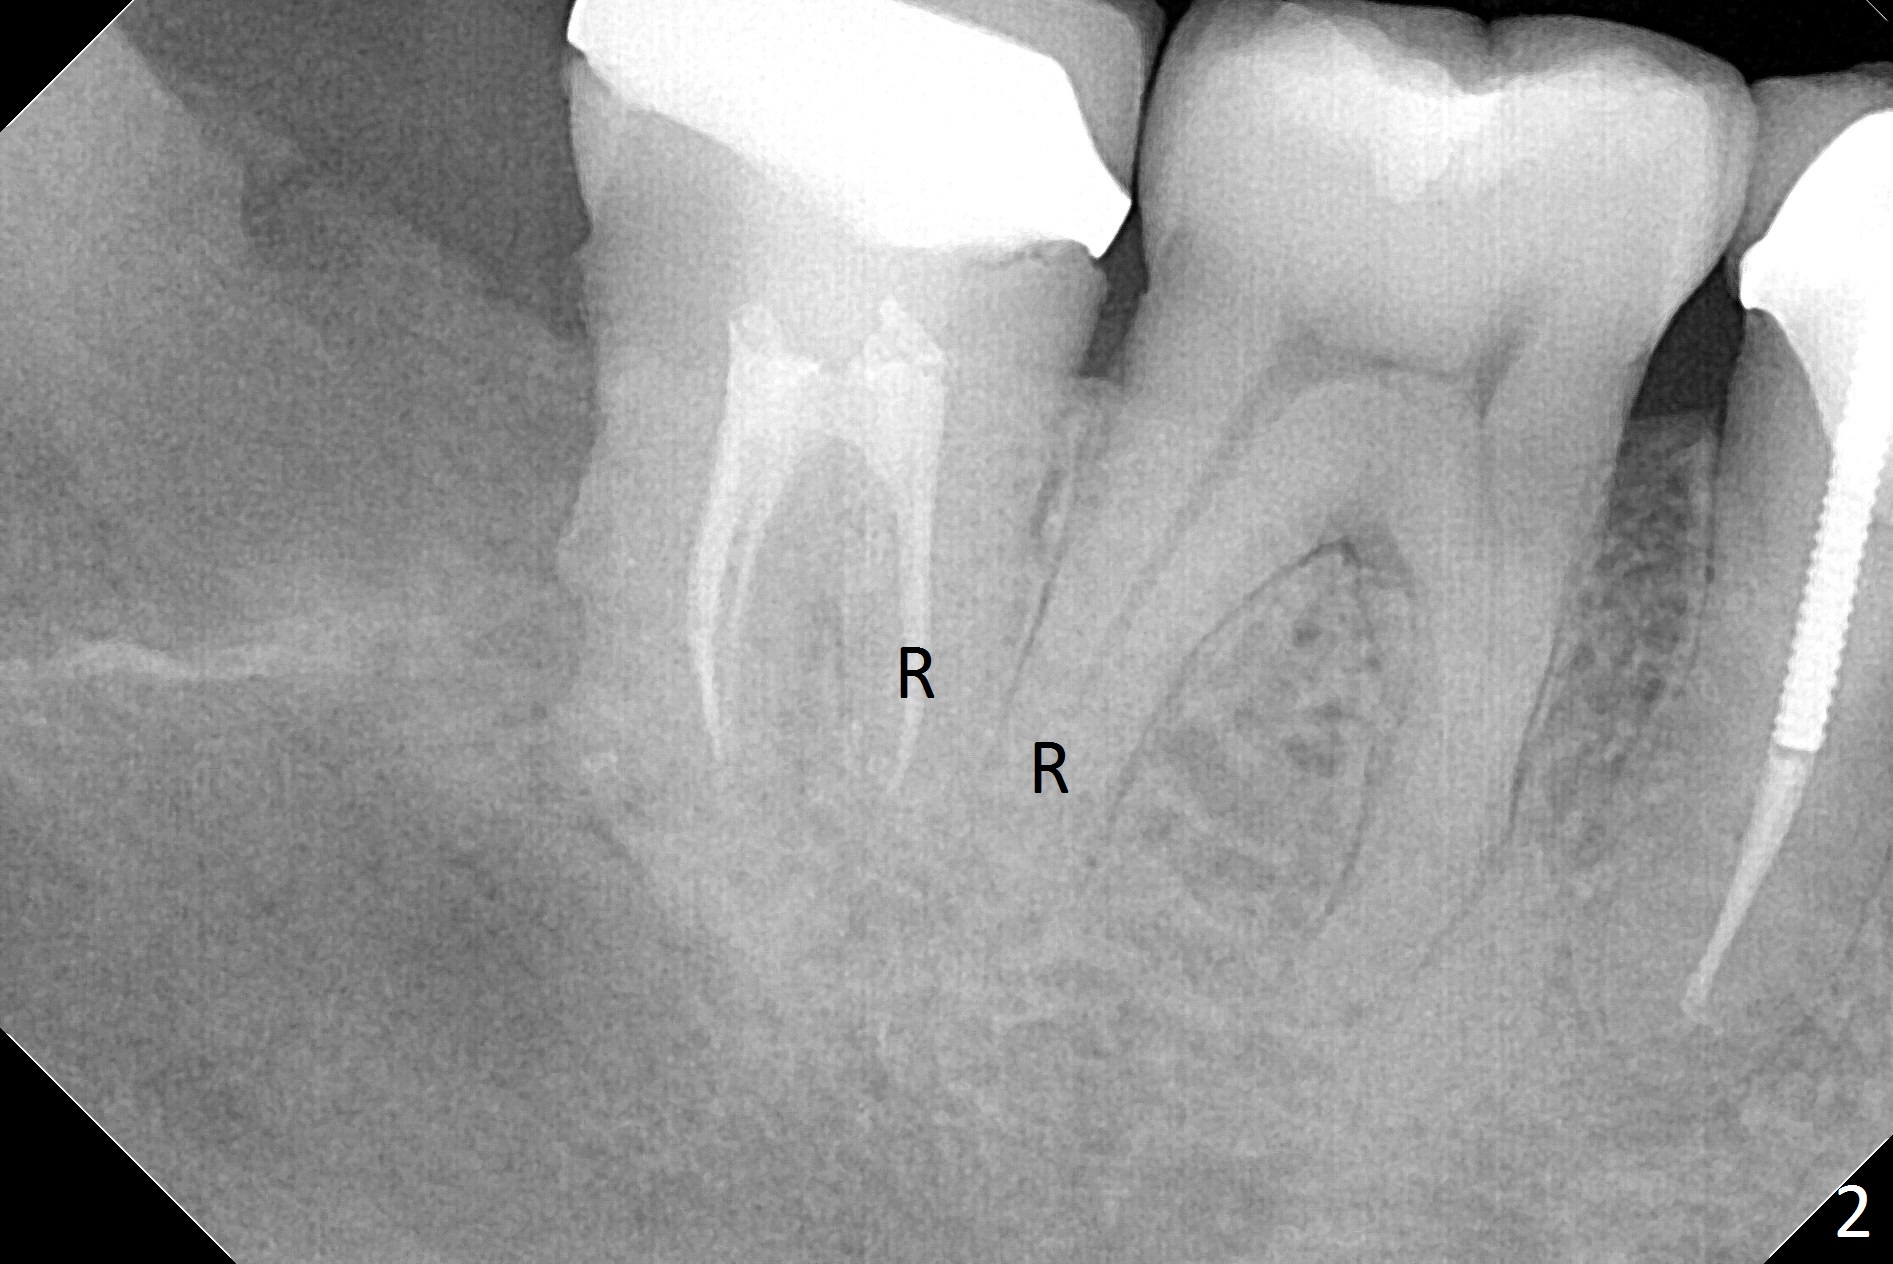

A 45-year-old woman presents to clinic with swelling and pain from the lower right posterior region. The tooth #32 is fully bony impacted. The distolingual gingiva of #31 is erythematous with deep pocket. The tooth is sensitive to percussion. Preop panoramic X-ray shows a radiolucent lesion between #31 and #32 (Fig.1 blue dashed line). Initial impression is infection from #32. Extraction of the latter turns out to be difficult. Purulent discharge is coming from underneath the coronal portion of the tooth. Curettage of the radiolucent lesion leads to hemorrhage. The curettage is not aggressive because of the underlying Inferior Alveolar Canal (red dashed line). Following copious irrigation, a 10x20 mm Osteogen plug is inserted into the socket with incision closure. Postop PA reveals that the roots the teeth #31 and 30 approximate to each other (Fig.2 R). In case the tooth #31 needs to be removed (Fig.3 black area), osteotomy for immediate implant will be established in the middle of the septal stump (Fig.5 red arrow) after removal of the coronal septum (Fig.4). CBCT may be necessary for determination of the osteotomy depth.